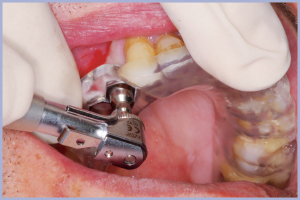

Si realizza la Dima Chirurgica e si programma l’intervento in sedazione cosciente perché il paziente è un soggetto ansioso, con la collaborazione della specialista in anestesia. La sedazione cosciente viene indotta con miscela di gas di protossido di azoto e ossigeno e benzodiazepina a emivita breve (Midazolam) in vena. Con questa tecnica il paziente mantiene i riflessi oro-faringei e risponde ai comandi a seconda dell’esigenza dell’operatore. Si esegue, comunque, l’anestesia locale per infiltrazione con articaina 1:100000, si inserisce la Dima Chirurgica e si esegue lembo mucoso con mucotomo circolare.

In seguito, si esegue la sequenza delle frese chirurgiche con stop e diametri e lunghezza pianificati con sistema Real Patient™ Guide System (3DIEMME® Srl, Cantù (Co)), si inseriscono gli impianti e i tappi di guarigione e si congeda il paziente senza aver eseguito il lembo chirurgico e punti di sutura (Figg. 1-38). I vantaggi della chirurgia guidata flapless sono un edema e dolore post- intervento minori, riduzione dei tempi di guarigione, assenza di riassorbimento osseo dopo esposizione con il lembo e minori disagi per il paziente (riduzione dei controlli, assenza di dieta liquida e assenza di rimozione dei punti di sutura) e per l’operatore (sicuramente riduzione dello stress). Ovviamente non sempre si può eseguire un intervento di chirurgia guidata a cielo coperto; è, infatti, indispensabile avere a disposizione un discreto osso in termini di qualità e quantità . Con questi presupposti il sistema assicura un’ottima predicibilità e la possibilità di effettuare anche un carico immediato con protesi provvisoria.

- Figg. 31-35 – Posizionamento guidato degli impianti

- Fig. 32

- Fig. 33

- Fig. 34

- Fig. 35